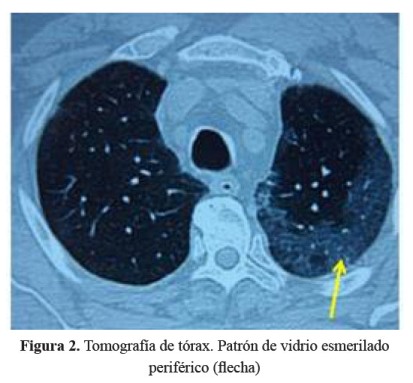

Se realizó una tomografía de tórax que mostró infiltrados intersticiales bilaterales con patrón en vidrio esmerilado en tercio medio e inferior a predominio del pulmón izquierdo (Figura 2), mientras que en las bases se observó patrón en panal de abeja con engrosamiento de los septos y bronquiectasias de tracción ( Figura 3).

El paciente tenía antecedente de insuficiencia cardíaca y de fibrilación auricular paroxística por lo que recibía tratamiento con amiodarona, acudió con una historia de 3 semanas de tos, disnea y fiebre, llamando la atención desde el ingreso la radiografía de tórax con infiltrado bibasal tipo consolidado pero también con compromiso intersticial en la periferia. Recibió tratamiento para neumonía adquirida en la comunidad con ceftriaxona y claritromicina, además diuréticos por el antecedente de insuficiencia cardíaca. La evolución fue estacionaria, se cambió la cobertura antibiótica a ceftazidima y amikacina; sin embargo, la fiebre persistió. La tomografía de tórax confirmó lo que se evidenciaba en la radiografía, un compromiso intersticial difuso, con áreas de patrón en vidrio esmerilado en la periferie y patrón en panal de abeja en bases.

Por el antecedente de uso de amiodarona a dosis de 200 mg diarios por 1 año y medio y el compromiso intersticial, otra posibilidad diagnóstica sería toxicidad pulmonar por amiodarona, en el que se describe infiltrados en vidrio esmerilado en la periferie, compromiso reticular en bases, y zonas de atenuación aumentada por acumulo de yodo en el parénquima pulmonar simulando lesión tipo masa pulmonar solitaria (2). En esta enfermedad se encuentran células espumosas en el lavado bronquioloalveolar (LBA), que son complejos de macrófagos con lípidos, que no son diagnósticas puesto que también se encuentran en pacientes que reciben amiodarona pero sin cuadro de toxicidad pulmonar (3); si no lo presenta es excluyente.